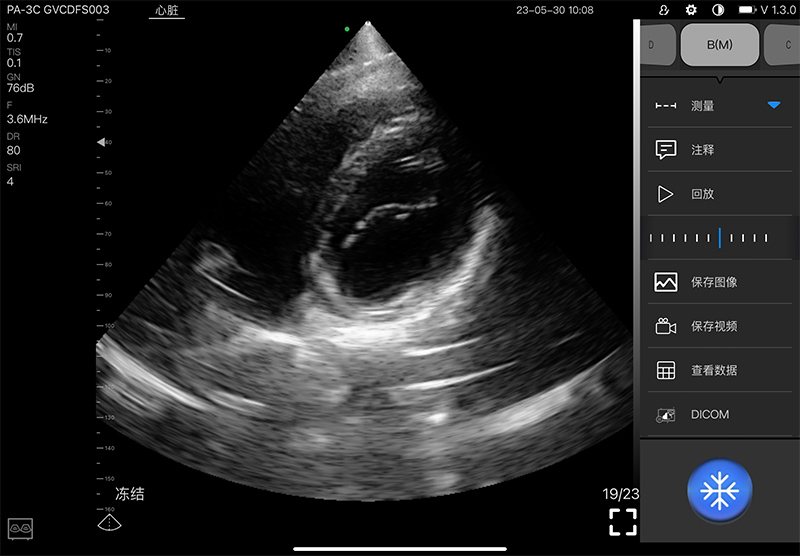

- Scanning mode: Electronic phased array

- Elements: 128

- Channel: 32

- Display mode: B, B/M, and Color, PW, CW, PDI

- Frequency: central 2.8MHz, cardiac reverse harmonic

3.6mhz, and the transcranial fundamental 2.2MHz

- Display Angle: 80°

- Display Depth: 90/160/200/240mm

- Image Adjust: Gain, DYN, Focus, Depth, Harmonic, Denoise

- Noise reduction: 0-1-2-3-4

- Gain: 30db-105db

- Dynamic Range: 40/50/60/70/80/90/100/110

- Measure: Length, Area, Angle, Heart

- Image frame rate: 15~20 framescond